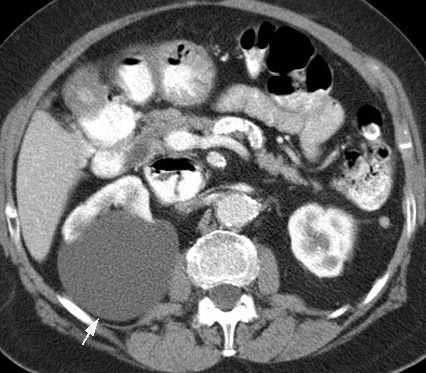

Simple Renal Cyst:

Contrast CT characteristics:

Complicated Cyst should be considered when there are:

A simple cyst can be complicated by either infection, carcinoma, or hemorrhage